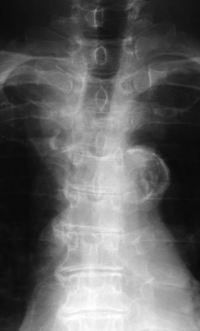

血液所見:赤血球 413 万、Hb 12.0 g/dL、白血球 7,200、血小板 27 万。血液生化学所見:総蛋白 7.3 g/dL、アルブミン 4.2 g/dL、尿素窒素 13 mg/dL、クレアチニン 0.8 mg/dL、AST 40 U/L、ALT 24 U/L、LD 768 U/L (基準 176〜353)、ALP 997 U/L (基準 115〜359)、Na 144 mEq/L、K 4.8 mEq/L、Cl 105 mEq/L。CRP 1.4 mg/dL。胸椎エックス線写真、頸胸椎MRIのT2強調矢状断像及び第3胸椎レベルの水平断像を別に示す。